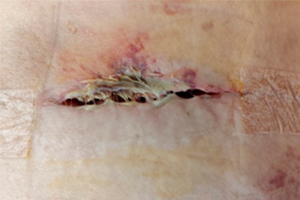

Apresenta deiscência de sutura

Reconsulta, retirada da fita adesiva apresenta deiscência de sutura, ferida operatória com presença de tecido desvitalizado, necrose de coagulação. Conduta adotada: Rifocina spray.